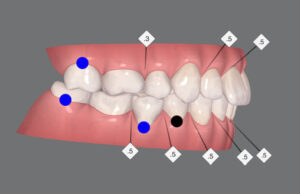

この歯並びが治る原理はⅡ級ゴム

上の歯列を後ろに動かす

えんしん移動

出っ歯を矯正